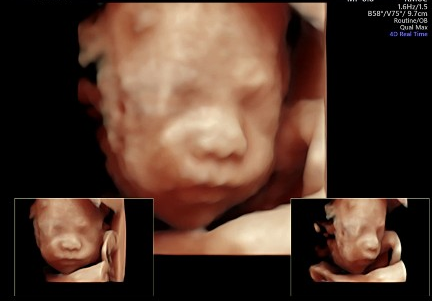

2차 정밀초음파도 봤는데

마지막은 최신자 아들래미 초음파 사진으로!

일단 코는 나닮은듯.